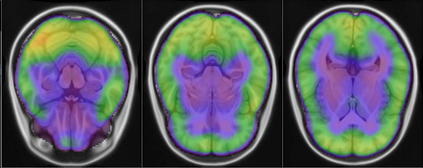

Representational similarity analysis (RSA) is a multivariate technique to investigate cortical representations of objects or constructs. While avoiding ill-posed matrix inversions that plague multivariate approaches in the presence of many outcome variables, it suffers from the confound arising from the non-orthogonality of the design matrix. Here, a partial correlation approach will be explored to adjust for this source of bias by partialling out this confound. A formal analysis will show the dependence of this confound on the temporal correlation model of the sequential observations, motivating a data-driven approach that avoids the problem of misspecification of this model. However, where the autocorrelation locally diverges from the volume average, bias may be difficult to control for exactly (local bias), given the difficulties of estimating the precise form of the confound at each voxel. Application to real data shows the effectiveness of the partial correlation approach, suggesting the impact of local bias to be minor. However, where the control for bias locally fails, possible spurious associations with the similarity matrix of the stimuli may emerge. This limitation may be intrinsic to RSA applied to non-orthogonal designs.